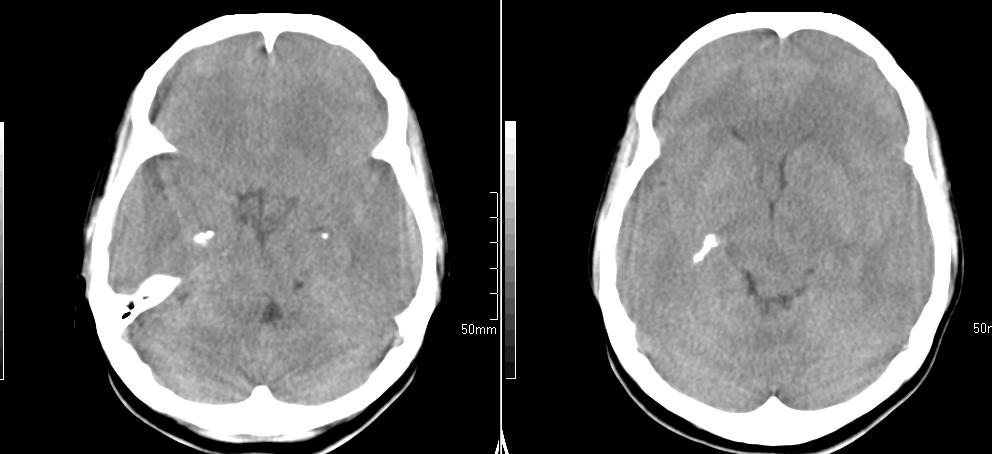

标题: CT23966:女,34岁,近一月头痛、意识障碍 [打印本页]

标题: CT23966:女,34岁,近一月头痛、意识障碍

左侧额叶见不规则软组织影,部分囊变,病变略呈等密度,占位效应明显,考虑血母可能。脑膜瘤不除外

左侧额叶肿瘤样病变,成等密度,其内可见囊变,肿瘤似与大脑镰相连,周围水肿不明显。考虑脑膜瘤可能!建议强化或mri。

左额叶囊实性肿块,实性部分呈等密度,密度不均,考虑胶质瘤可能性大,脑膜瘤及室管膜瘤不除外,建议mri增强扫描。

左额叶较大等低混杂密度影,占位效应明显,首先考虑:左额叶胶质瘤。